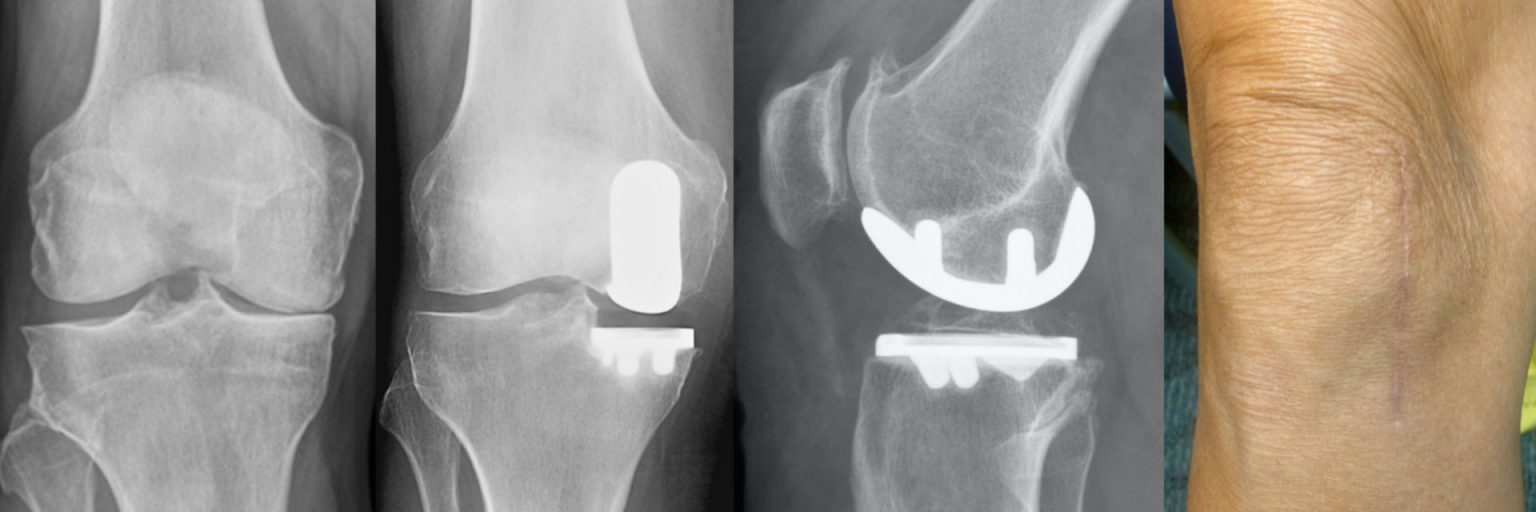

Partial Knee Replacement CuttingEdge Surgery & Rapid Recovery

Partial Knee Replacement Procedure Can You Ski With A Partial Knee Replacement You want to avoid skiing terrain. the short answer. Soft powder is ideal for easing your new joint into ski shape and reducing injuries from falls. Be aware of snow conditions. This leaves surgeons with little information for. while experienced skiers should be able to ski after knee replacement, you may have to make some accommodations. As a. Can You Ski With A Partial Knee Replacement.